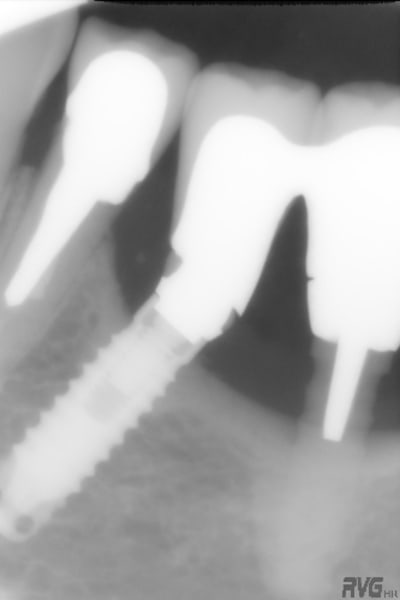

pour le débat, voici ce que j'ai posé en 1990, 1 TBR vissé + 2 zircones vissés de Sandhaus, et voici le résultat 17 ans plus tard. comme le mélange des genres va interpeller, j'explique. il s'agit là de la 2ème pose d'implant de ma carrière débutante, alors que je faisais le DU de la Salpétrière. c'était à l'époque où l'on débatait sur le risque de solidariser un implant à une dent. j'ai finalement préféré ne pas solidariser mes 2 implants 36-37 à la 34 et j'ai donc rajouté un implant en 35 par la suite; entre temps, j'avais abandonné les implants en zircone car la technique chirurgicale proposée avec ne me plaisait pas et que celle proposée pour les implants en titane me convenait davantage. il s'agissait déjà pour Sandhaus de poser les implants sans faire de lambeau et pour le débutant que j'étais, je trouvais ça trop délicat; j'ai donc terminé le cas avec un TBR en technique Branemark plus sécurisante.